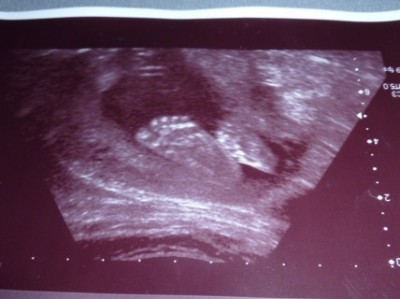

ich bin soooooooo glücklich unser Maus bleibt ein Mädchen und ist 26cm un 414g leicht!